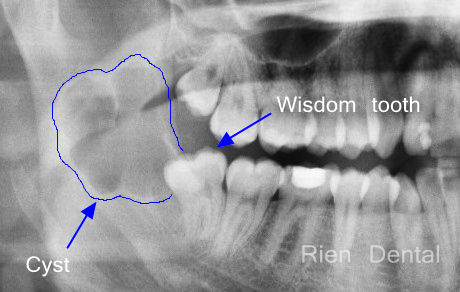

Impacted wisdom teeth may cause pain, decays and gum inflammation. But sometimes wisdom teeth can cause more serious problems.

In this case, a large infection cyst associated with lower right mandibular wisdom tooth gave the patient severe pain. The patient had to be managed by a oral and maxillary surgeon who performed an urgent operation to remove the cyst and wisdom tooth under general anesthetics. The pathology showed it was an odontogenic keratocyst.